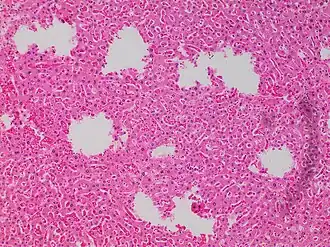

![Tearing artifacts, such as can be caused by: - Microtomy with a nick or blemish in the knife edge.[5] - Traction of the sections. - Too much or too little alcohol dehydration.[5] - Sectioning calcified parts, which can be decalcified or removed.[5]](./_assets_/Microscopy_of_liver_parenchyma_with_tearing_artifacts.jpg)

In microscopy, an artifact is an apparent structural detail that is caused by the processing of the specimen and is thus not a legitimate feature of the specimen. In light microscopy, artifacts may be produced by air bubbles trapped under the slide's cover slip.[1]